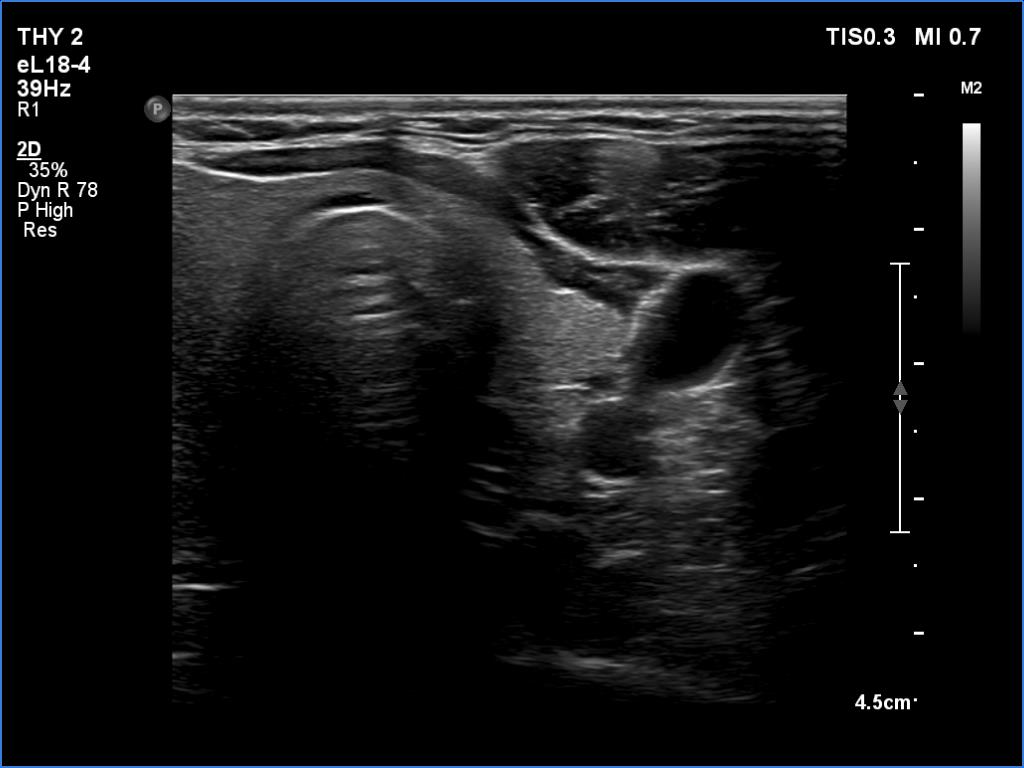

The operated thyroid - case 1641 (ultrasonographic picture 8)

Left lobe, transverse scan. This lobe is decreased in size.